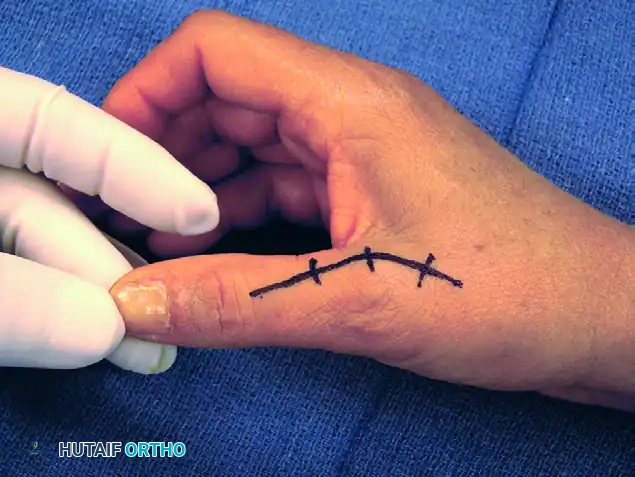

1. Incision and Superficial Dissection

The procedure begins with a carefully planned incision designed to maximize exposure while protecting critical structures.

- Make a curved dorsal incision centered over the MCP joint. The apex of the curve should be positioned slightly ulnar or radial to the midline to prevent a straight-line scar contracture directly over the joint space.

- Carefully dissect through the subcutaneous tissues. Identify and gently retract the terminal sensory branches of the superficial radial nerve using vessel loops.

FIGURE 73-40A: Curved dorsal incision to allow safe dissection of sensory nerves from the underlying extensor apparatus.